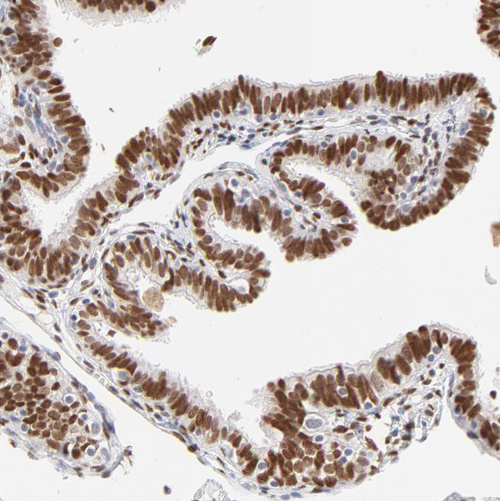

Immunohistochemistry analysis in human fallopian tube and liver tissues using HPA003881 antibody. Corresponding PBX1 RNA-seq data are presented for the same tissues.